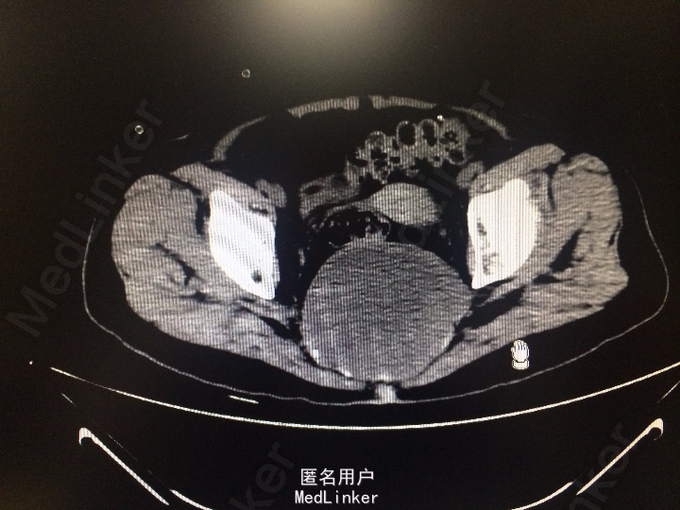

老年女性 主诉:腰背痛半年余,大小便失禁1周。 病史:患者于半年前腰部扭伤后,出现腰痛、腰部无力,需借助外力站立和行走。自诉四肢肌肉力量间断出现减弱,容易出现肌肉僵直,并有肌肉颤动感。半年来,患者多卧床休息,未接受正规治疗。10余天前,出现胸部疼痛,并向背部放射,病人烦躁、易怒,难以入睡、胃纳差、大便次数少。1周前出现大小便失禁,体重近1月下降10余斤。

查体:脊柱生理弯曲存折,腰椎棘突间触痛(-),双侧腰椎旁叩痛(-),活动自如,关节无红肿,双侧下肢肌群肌力正常,双侧下肢外侧皮肤痛、温觉正常,未引出病理性反射,尾骨未触及。 辅查:外院X线:腰骶角增大,提示腰椎失稳可能;腰椎轻度退行变;S3以下骨质结构缺如。

诊断:骶尾部肿物:脊索瘤? 处理:完善各项检查后,为明确具体病理类型行骶尾部肿瘤穿刺活检术,病理明确后行腹腔镜辅助下骶尾部肿瘤切除术。